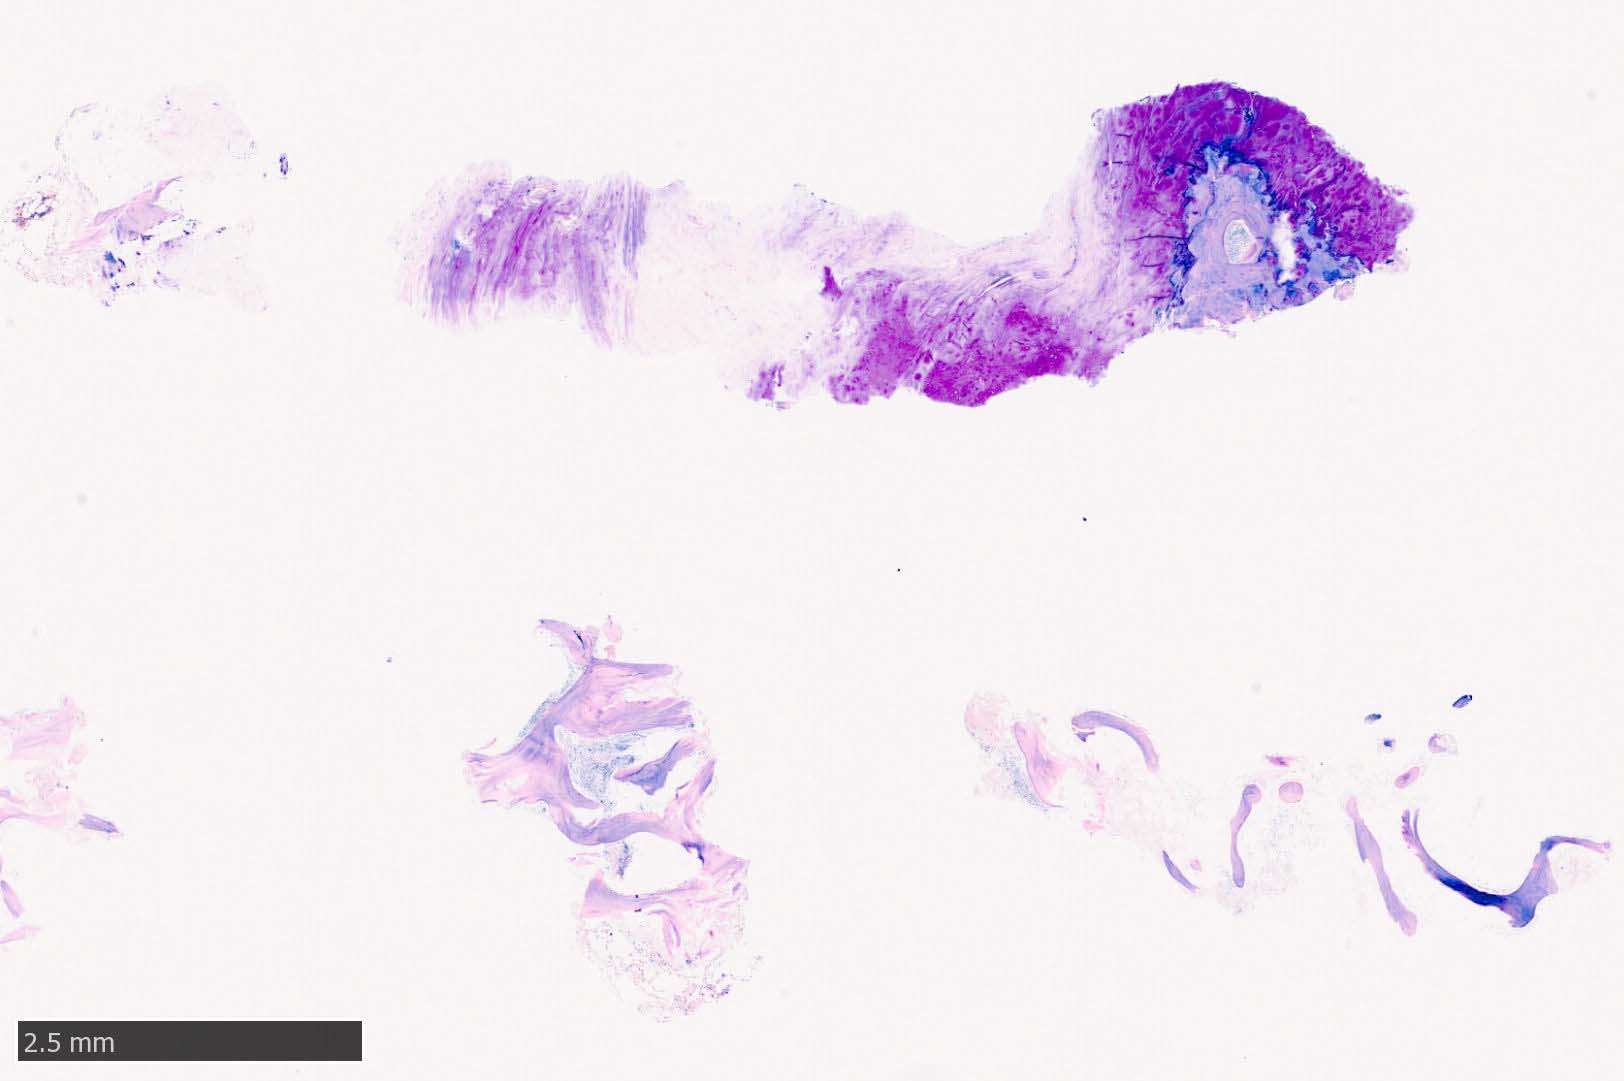

骨髄生検組織所見

骨髄生検組織では骨梁間に壊死に陥った細胞の凝固壊死像が確認できる. 本例では脂肪細胞は消失せず形態が残っている.壊死のあとには, 髄腔に線維化をきたす. 上図には線維化を示し, 右端の図では壊死巣と線維化の境界が観察される.